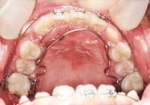

下記にて神谷歯科クリニック症例写真で確認できますが、歯の裏側にワイヤーを付け調整します。

したがって歯の表からワイヤー金属は見えず、笑っても矯正していないように見えます。

一般的な舌側矯正治療の方法と手順

A・Y 女性 27歳

治療名:舌側矯正、マルチブラケット

接客業など間近で会話をすることが多い方で、装置を見せたくない場合は歯列の裏側にブラケットを付けて歯を動かします。

治療期間・回数:4年6か月、52回

治療に関するリスク・副作用:成人の方が多く行いますが、歯周病や虫歯、根の治療をジ事前に行う必要があります。表側よりも治療期間が長くかかる場合があります。